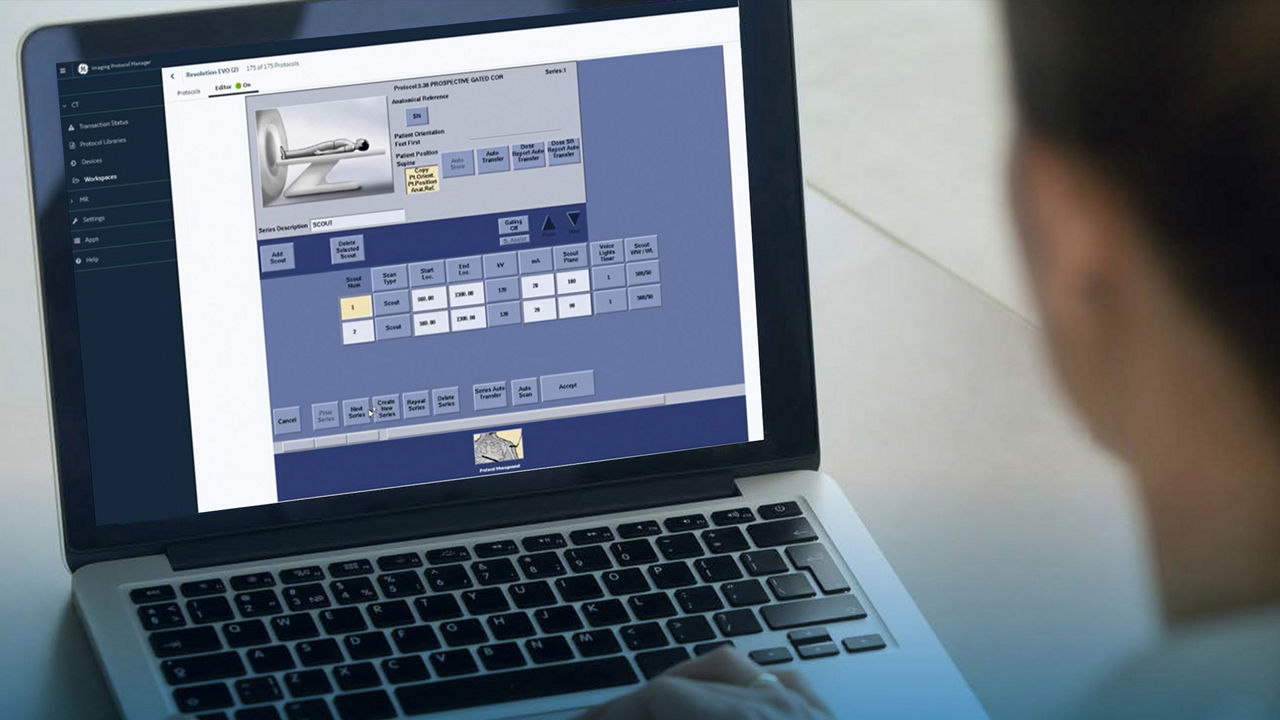

Leveraging transformational imaging technology to realize the promise of precision medicine and help deliver better outcomes. Our medical imaging products range from systems, including MRI, CT, PET, SPECT, Ultrasound, Mammography and X-ray, to digital and AI solutions to help drive healthcare digitialization, help enable faster exam workflow, improve clinical outcomes and increase efficiencies.